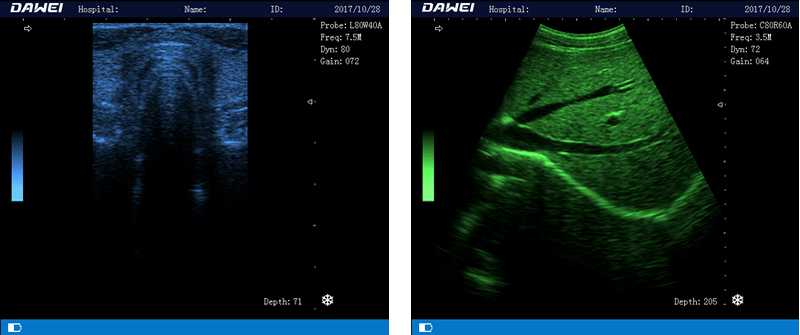

DW-580

筆記本全數(shù)字超聲診斷儀

1.優(yōu)質(zhì)的數(shù)字成像技術(shù),圖像更清晰